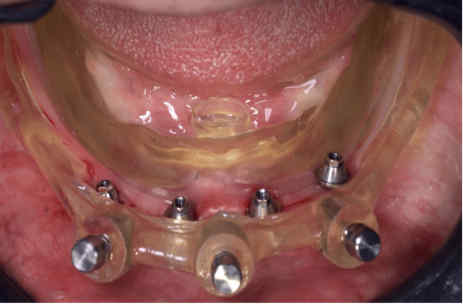

The provisional prosthesis was directly relined and secured using titanium abutments and flowable resin (Figures 9, 10). The installation of the temporary prosthesis for immediate loading was performed (Figure 11). The final panoramic radiograph and tomography image showing the result was obtained, revealing the implant placement with immediate provisional fixed rehabilitation (Figures 12, 13).

FIGURE 10: Capture of the prosthesis with flow resin and closure of spaces outside the mouth*

*Coifa for Mini-conics Implacil – Osstem

FIGURE 11: Installation of the temporary prosthesis for immediate loading